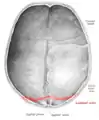

Lambdoid suture (labeled at bottom right)